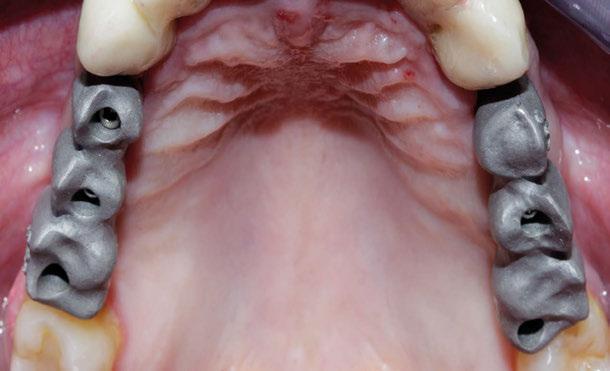

Desde el laboratorio Ávila Mañas S.L. todos nuestros esfuerzos van dirigidos a garantizar la mejor calidad y no el precio más bajo. Sabemos que la calidad, seriedad y garantía tienen precio Avila Mañas. Advanced Aesthetics & Fundation | C/ Ramón Calabuig 57, 28053-Madrid. Spain Tel.: +34 91 478 21 83 | Fax: +34 91 477 77 16 labavila@avilam.com | www.avilam.com ESTRUCTURA CAD-CAM FRESADA ESTRUCTURA FRESADA CAD-CAM CON CERÁMICA PERSONALIZADA CIRCONIO CERÁMICA PERSONALIZADA CIRCONIO CERÁMICA SOBRE IMPLANTES CARILLAS PERSONALIZADAS CORONAS E-MAX CAD-CAM FRESADAS CORONAS INDIVIDUALES E-MAX CAD-CAM